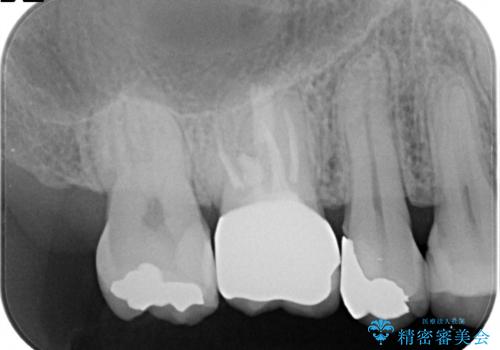

【MTAを用いた生活歯髄療法】神経に到達する深い虫歯

- 以前入れていた、詰め物が取れたことを主訴に来院されました。

虫歯が深く、神経の部屋まで達していました。

術前の検査から、神経が保存できる可能性が高いため部分的断髄法を選択し治療を行いセラミックインレーにて修復しました。

褐色の歯質を認めますが、テトラサイクリンによる変色のためカリエスの残存はありません。